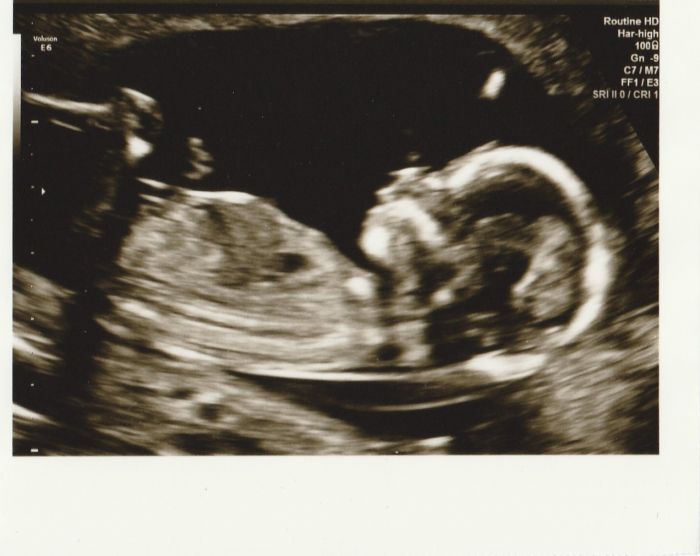

[498651] moc te tu vitam mezi tehule :-) A v kolikatem jsi tydnu? jinak krasna fotecka .mame tu udelanou tabulku ale ony te holky urco dopisou ;-)